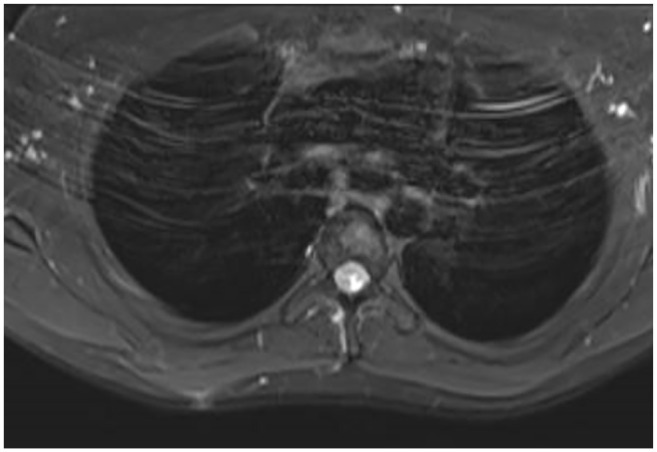

Rhomboid tears are a rare type of tendon injury. Although rhomboid tears can present with periscapular pain and scapular dyskinesis, their clinical presentations and diagnostic procedures remain largely unknown. In addition, few reports are available on the surgical treatment of rhomboid tears. We report a rhomboid repair case for a complete rhomboid major tear diagnosed based on physical findings and magnetic resonance imaging (MRI). A 28-year-old man presented with right medial scapular pain that appeared after carrying a heavy box. He had right medial scapular tenderness, with worsening pain during shoulder joint elevation. The inferior pole of the right scapula was lateral compared with the left scapula, and a dent was observed on the medial scapula. Magnetic resonance imaging revealed a tear in the right rhomboid major at its insertion, with muscle retraction. Two months of conservative treatment failed to improve his symptoms; therefore, we performed a surgical repair. We created the bone holes on the medial border of the scapula and repaired the torn rhomboid major muscle to its insertion using the Krackow stitch technique. He had a satisfactory functional outcome without postoperative retearing. This case report provides new information on the clinical presentation and surgical procedure of rhomboid major tears and the first MRI finding that depicts a rhomboid tear clearly. In cases of rhomboid tears, persistent medial scapular pain and winging scapula can be clinically problematic, requiring surgery. In addition to physical findings, a periscapular MRI is useful in diagnosing rhomboid tears. The results of this case study suggest that surgical repair using locking sutures is an option for treating complete rhomboid tears with muscle retraction.